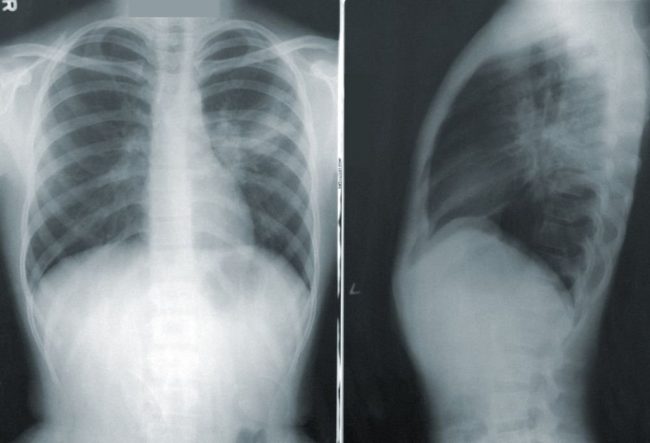

Просветим: ученые Пермского Политеха рассказали, какие болезни выявляют рентген, КТ и МРТ Первый рентген-снимок был сделан в 1895 году, и показывал лишь небольшое затемнение на фотопластинке. В наши дни излучение помогает диагностировать заболевания любых тканей организма, а также планировать операции в виртуальном формате. Ученые ПНИПУ объяснили, как работают рентген, КТ и МРТ и в чем…